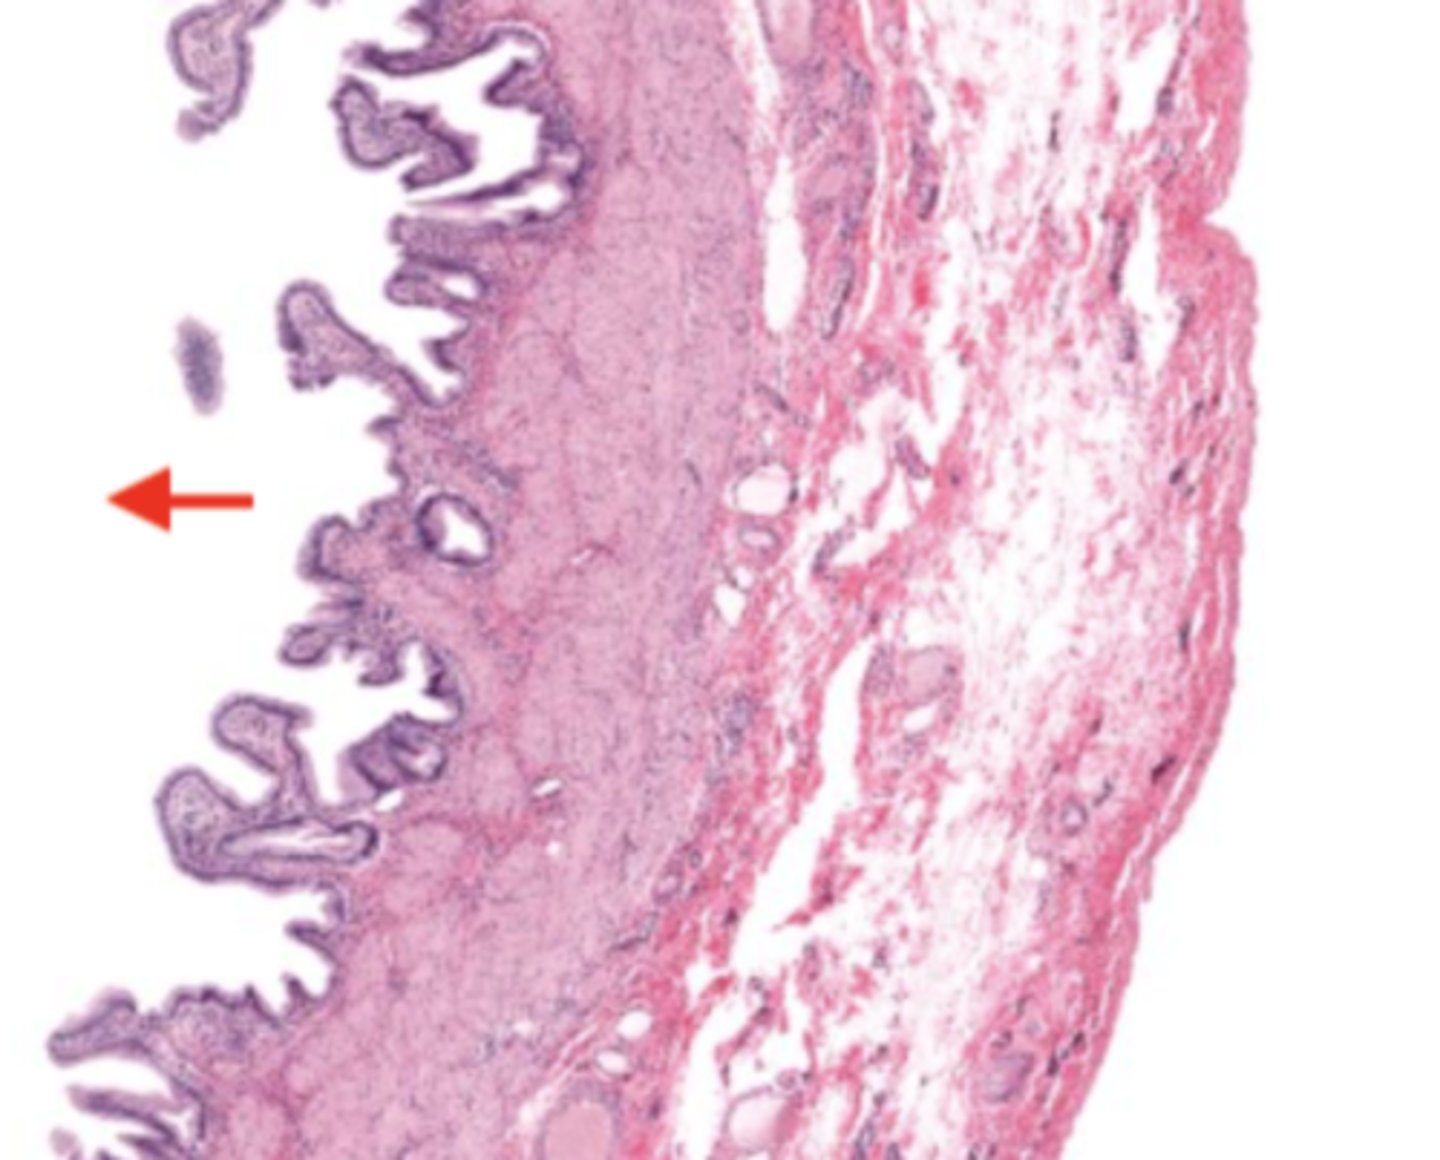

gallbladder (histology)

gallbladder

this tissue's wall structures/layers are different than the rest of the organs

simple columnar epithelium

what kind of epithelium lines the mucosa of the gallbladder

lumen (gallbladder)

mucosa (gallbladder)

mucosal epithelium (gallbladder)

lamina propria (gallbladder)

muscularis mucosa and submucosa

gallbladder tissue does not have _______ and ______

muscularis externa (gallbladder)

serosa/adventitia (gallbladder)